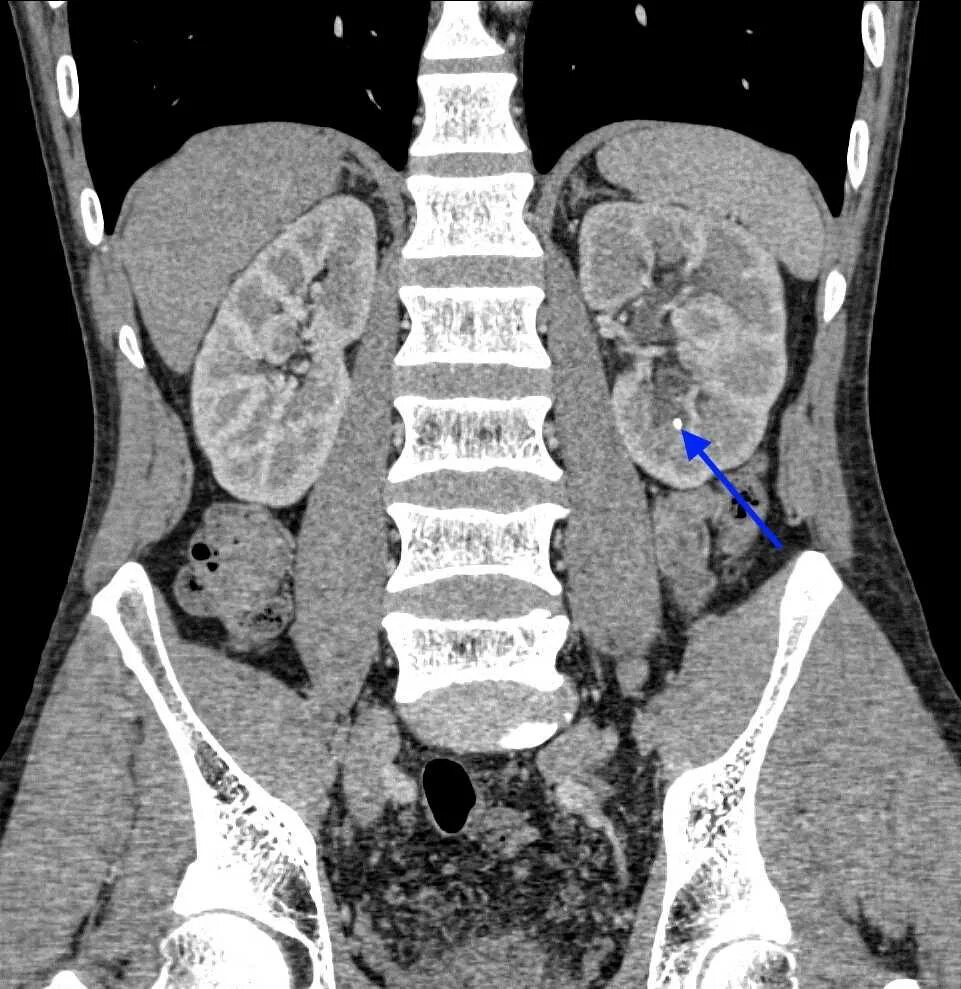

Кт мочевыводящих путей